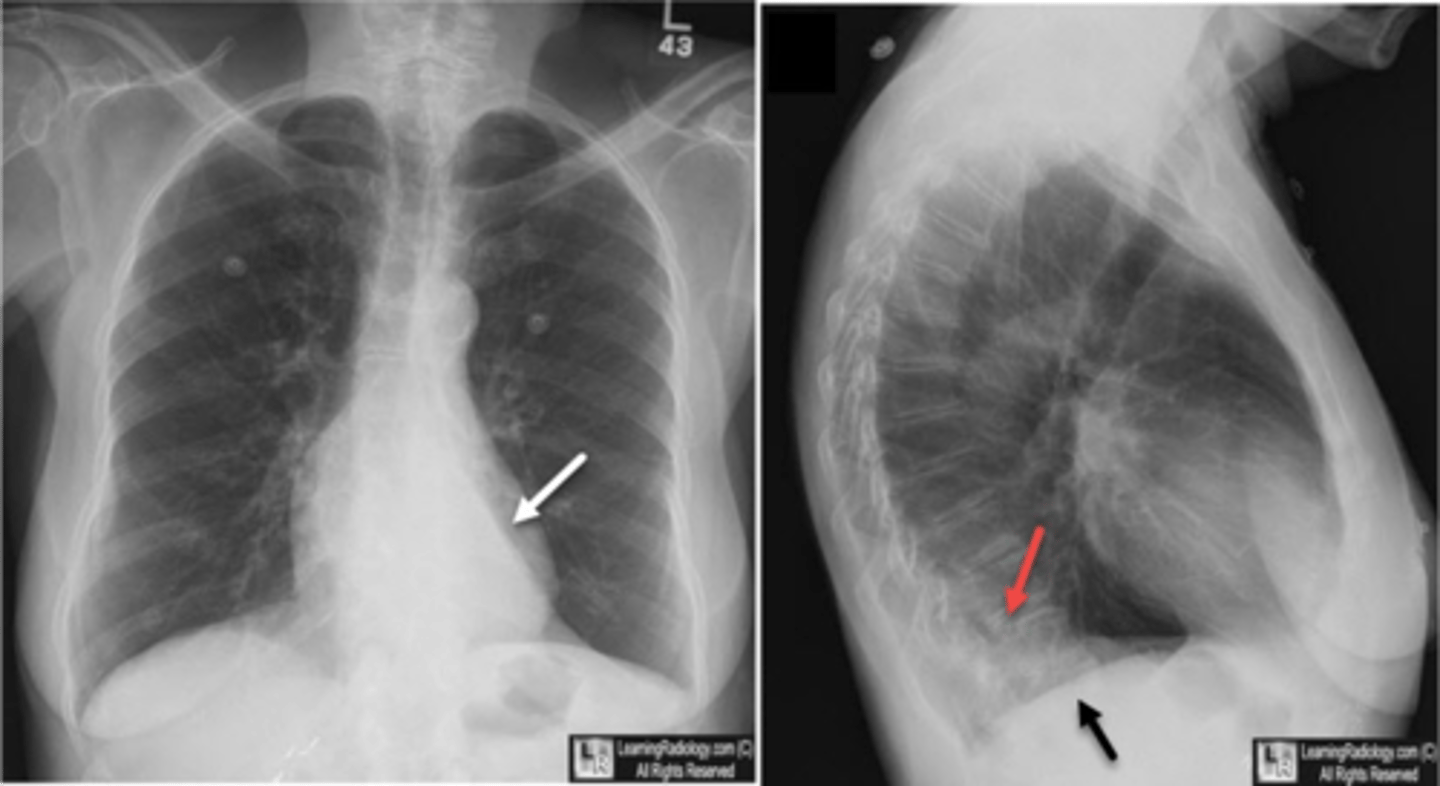

Pleural effusion

Pleural effusion

Pleural effusion (right sided)

Empyema

Empyema